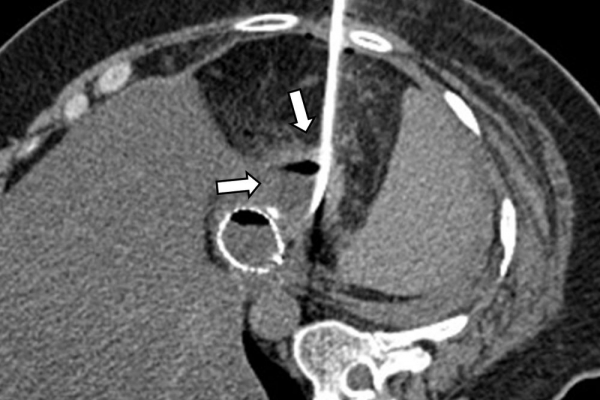

Η παρέμβαση διενεργείται υπό την καθοδήγηση αξονικού τομογράφου ή υπερήχων ή και με συνδυασμό τους. Ο επεμβατικός ακτινολόγος αρχικά αναισθητοποιεί την ανατομική περιοχή ενδιαφέροντος με τη χρήση τοπικής αναισθησίας και παρακεντεί την συλλογή διαδερμικά με λεπτή βελόνη. Στη συνέχεια μέσω ομοαξονικών συστημάτων συρμάτων-καθετήρων-διαστολέωντοποθετείται διαδερμικός καθετήρας τύπου pig-tail εντός της συλλογής, ο οποίος συνδέεται με εξωτερική παροχέτευση.